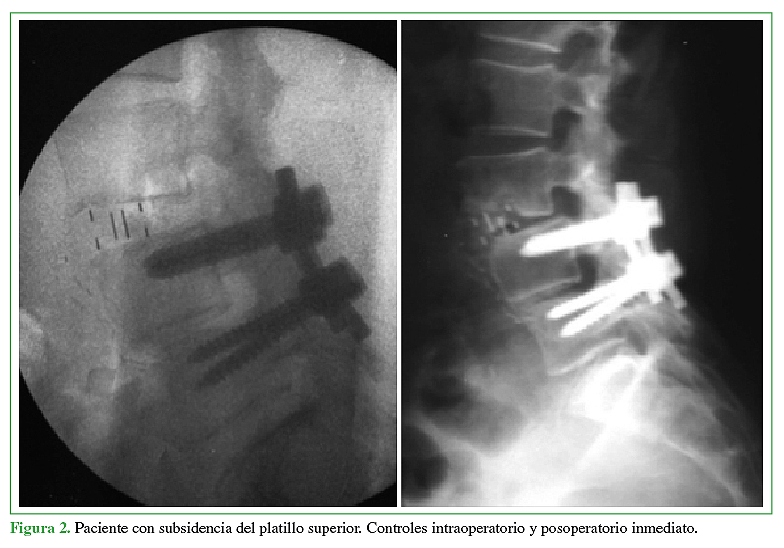

Le TV, Baaj AA, Dakwar E, Burkett CJ, Murray G, Smith DA, et al. Subsidence of polyetheretherketone intervertebral cages in mini- mally invasive lateral retroperitoneal transpsoas lumbar interbody fusion. Spine 2012;37:1268–73.

Marchi L, Abdala N, Oliveira L, Amaral R, Coutinho E, Pimenta L. Radiographic and clinical evaluation of cage subsidence after stand- alone lateral interbody fusion. J Neurosurg Spine. 2013;19:110–8.